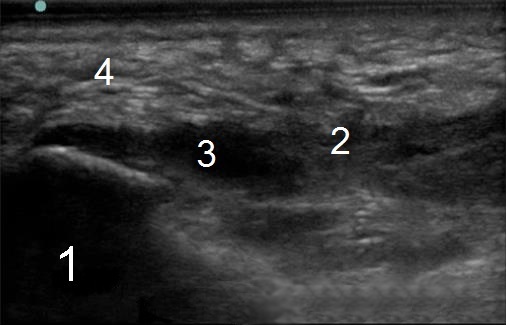

Bild 2: Fuß und Sprunggelenk, Ruptur der Aponeurosis plantaris

1. Rechts

2. Teile des Stumpfes der Aponeurosis plantaris

3. Lage der Ruptur/des Risses

4. Fettkörper